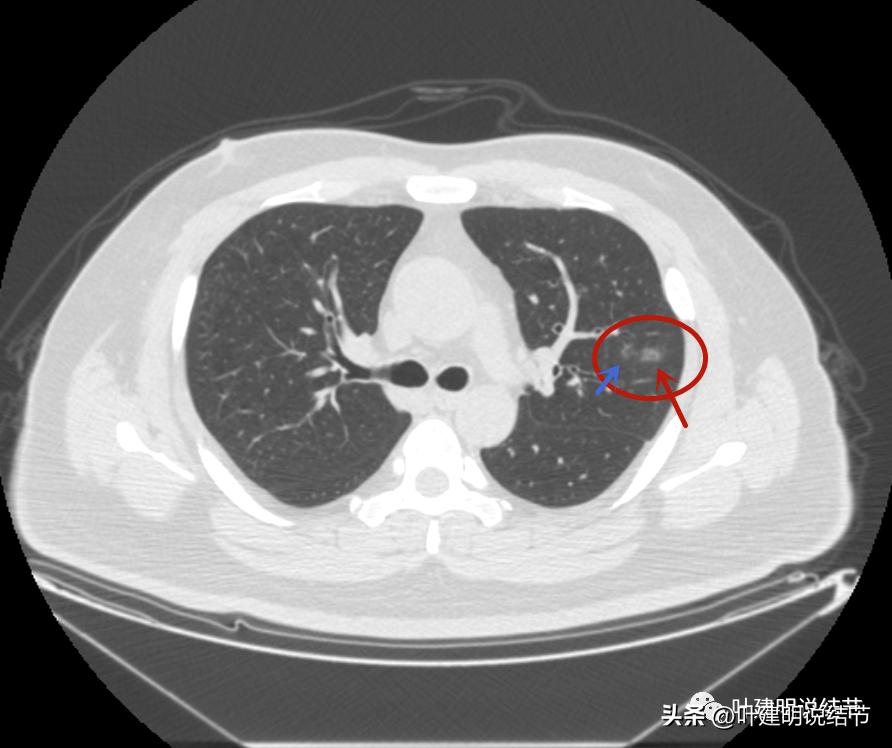

左上病灶1:磨玻璃结节,轮廓清楚伴微血管进入,中间似乎有空泡征,感觉像原位癌或不典型增生;

左上病灶2:混合磨玻璃结节,密度偏高,边缘稍糊,但轮廓相对清,有微血管分支进入,考虑微浸润性腺癌或浸润性腺癌可能大;

左上病灶3:混合磨玻璃结节偏实性,内部密度不均,整体轮廓清,有浅分叶,也有小血管关系密切,考虑浸润性腺癌可能性大;

左上病灶4:舌段磨玻璃结节,边缘显力糊,整体轮廓较清,不典型增生可能性大点。